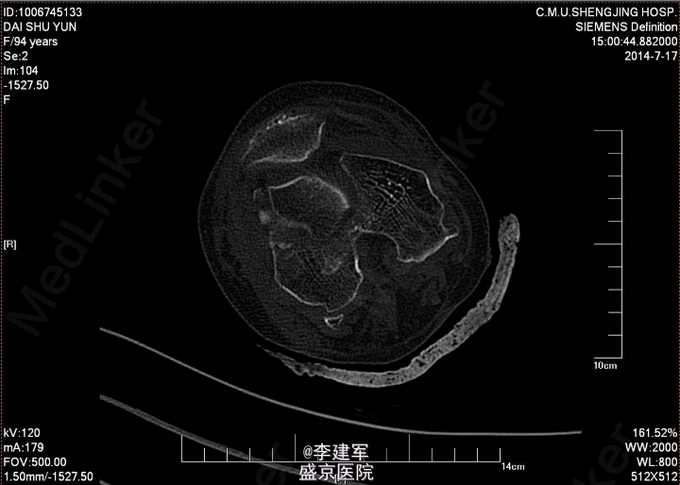

右股骨髁上粉碎性骨折 患者高龄,完善心电图,肺部CT,生化检查等,查无手术禁忌症。择期手术治疗。 手术拟行右股骨髁上粉碎性骨折闭合复位内固定术。 决定使用Liss钢板

患者高龄选用Liss钢板做闭合复位,减小手术创口。